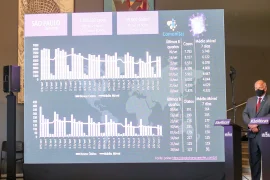

Em nova atualização, Bauru ocupa a 8ª posição no ranking de cidades que mais vacinam em SP

Governo de SP lança ranking de cidades que mais vacinam contra o coronavírus

Vacinação em SP é quatro vezes mais rápida que registro de novos casos de COVID-19

Com melhora de índices, dez regiões progridem de fase no Plano SP; Bauru permanece na vermelha

Região de Bauru tem a maior taxa de ocupação de leitos do Estado